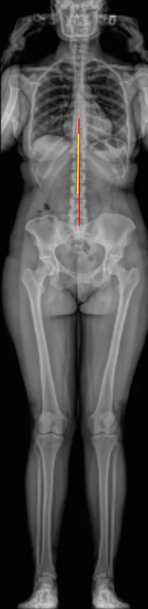

The Apical Vertebral Translation (AVT) quantifies the lateral displacement of the apical vertebra from the central vertical axis of the body in the coronal plane.

The apical vertebra is defined as the most laterally deviated and rotated vertebra at the midpoint of a spinal curve.

• Draw the Central Sacral Vertical Line (CSVL):

• Identify the center of the sacrum (S1 endplate midpoint).

• Draw a vertical plumb line extending upward through this point to the top of the image.

• Mark the center of the apical vertebral body (midpoint between the lateral borders of its endplates).

• Measure the horizontal distance (in millimeters) between the center of the apical vertebra and the CSVL.

• This distance is the Apical Vertebral Translation (AVT).